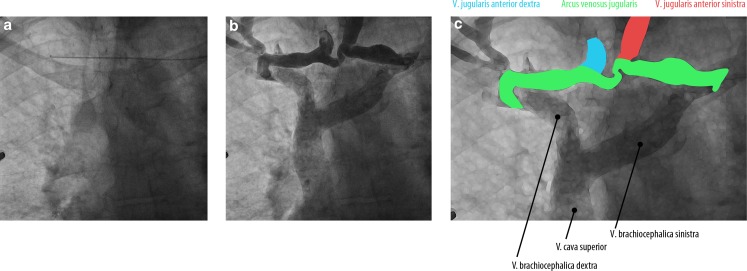

During pacemaker implantation, a remarkable anatomy of the jugular veins was noticed. An aberrant trajectory of the wire was perceived from the left subclavian vein to the contralateral side (Fig. 1a and online video). After contrast injection, two large veins were observed running parallel to one another which were connected caudally (Fig. 1b). Furthermore, the left brachiocephalic vein and superior vena cava (Fig. 1b and 1c) are appreciated.

Fig. 1.

a Chest radiography showing a guide wire (arrow head) running horizontally from the left subclavian vein to the contralateral side. b An overlay of sequential chest X‑rays showing a phlebogram of two anterior jugular veins running parallel (venae jugulares anteriores) which are connected caudally by a jugular arch (arcus venosus juguli). See also the online video

We concluded that the anatomy consisted of enlarged anterior jugular veins (venae jugulares anteriores) and a jugular arch (arcus venosus juguli) [1]. This is a common anatomy, but these jugular veins are rarely enlarged [2]. Probably, this has to do with the increased venous pressure due to backward heart failure.